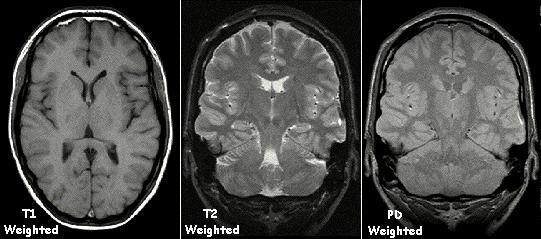

MRI의 영상을 나타내는 용어는 다음과 같다.

T1강조영상(T1 weighted image)이란 조직간의 T1이 서로 다른 데 따른 신호강도의 차이를 강조한 영상이다.

T1이란 종축이완시간(longitudinal relaxation time)으로서 고주파를 가한 후 원래의 축으로 돌아가는 데 걸리는 시간을 의미하며, 고주파를 반복해서 가하는 시간 사이의 간격인 반복시간(repetition time/RT)이 짧을수록 강조되어 나타난다.

T2강조영상이란 T2에 의한 조직간의 서로 다른 신호강도의 차이를 강조한 영상이다.

T2란 횡축이완시간(transverse relaxation time)으로서 고주파를 가한 후 수소 원자들이 서로 부딪치면서 원래의 축과는 다른 방향으로 돌아가는 데 걸리는 시간을 말하며, 반복시간이 길수록 강조되어 나타난다.

T1강조영상에서는 물은 검정색(신호강도가 낮음)으로 보이고, 지방이나 단백질 등은 농도의 차이에 따라 다르지만 회색 또는 흰색(신호강도가 높음)으로 보인다.

T2강조영상에서는 물이 반대로 흰색으로 보이고 지방이나 단백질은 그보다 어두운 색으로 보인다.